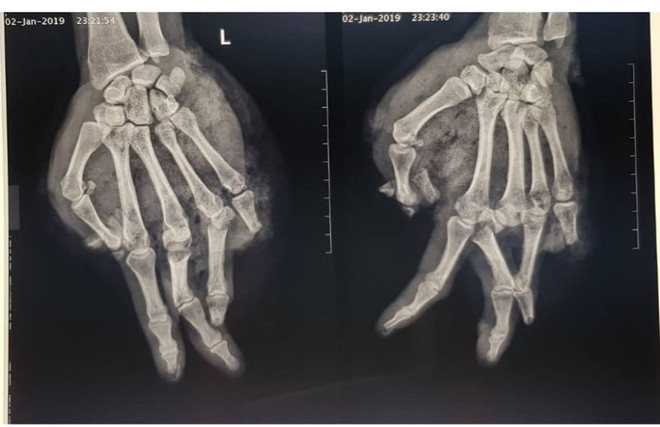

Bị bầm dập, lóc da bàn tay vì thay bình gas mini khi ăn lẩu ảnh 1Ảnh chụp phim X-quang bàn tay của bệnh nhân. (Ảnh: BVCC)

Bác sỹ Vũ Hữu Trung - Khoa Khoa Chấn thương Chi trên và Vi phẫu thuật, cho hay, qua quá trình thăm khám cho thấy, bệnh nhân bị tổn thương vết thương phức tạp, dập và lóc da, bầm dập nặng phần mềm bàn tay, dập nát ngón I, V và đốt 2,3 ngón IV; gãy hở nền xương đốt 1 ngón III, IV.